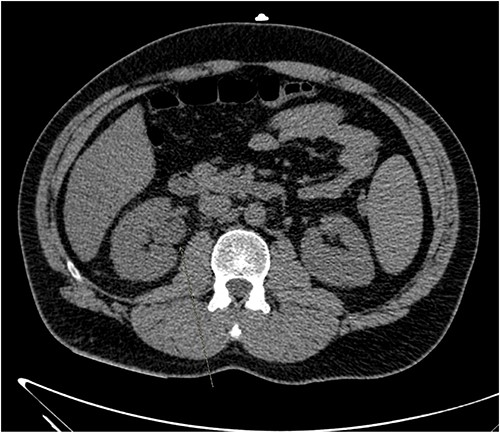

He presented with right sided abdominal pain associated with jaundice, fever, myalgia and arthralgia after receiving his second dose of the penultimate cycle of intra-renal BCG instillation. He did not have any tuberculosis contacts. His parameters on admission were stable. C-reactive protein levels were 230 mg/l and white cell count (WCC) was 6.51 × 109/l. His liver function tests were deranged, with a mixed obstructive and hepatitic picture. A CT kidneys, ureters and bladder (KUB) showed mild diffuse dilatation of the right ureter and renal pelvis with minimal amount of peri-ureteric fat stranding (Fig. 1). A CT scan of the abdomen with intravenous contrast (IV) was performed, this showed a distended right ureter down to the vesicoureteric junction, peri-ureteric fat stranding and lymphadenopathy in the aorto-caval space together with splenomegaly and atelectatic changes (Fig. 2).

An initial CT KUB showed mild diffuse dilatation of the right renal pelvis (as indicated by the arrow).